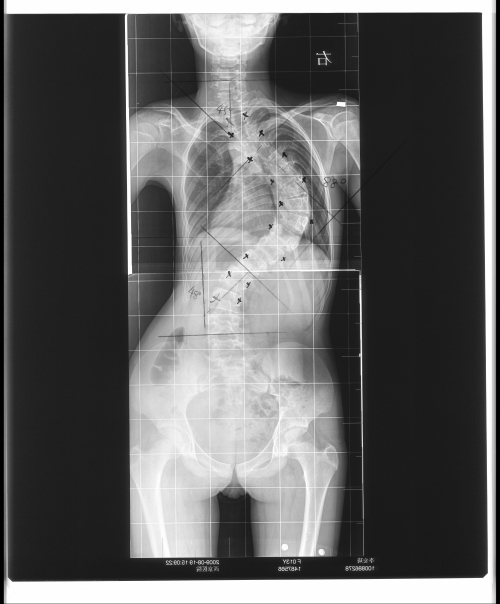

脊柱侧弯术前